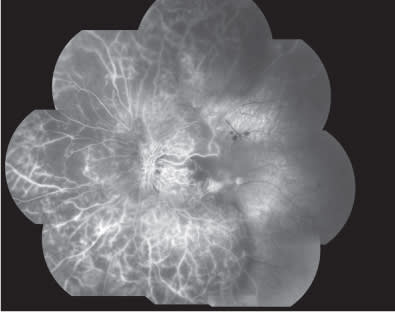

At baseline, best corrected visual acuity (BCVA) was 0.8 Snellen equivalent at right eye (RE) and 0.3 Snellen equivalent in the left eye (LE). Intraocular pressure was 14 mm Hg in both eyes. Slit-lamp examination of the anterior segment revealed nuclear sclerosis. Clinical examination of the retina revealed a nonproliferative diabetic retinopathy in both eyes, associated with the presence of clinically significant DME with hard exudative deposition in the LE (Figure 1). Central retinal thickness (CRT) on OCT was 223 μm and 551 μm in RE and LE, respectively, at baseline. Fluorescein angiography (FA) (Figures 2 and 3) disclosed more clearly the presence of the diabetic retinopathy with DME in the LE. The patient was advised to undergo intravitreal injection of ranibizumab.

Figure 2. Composite fluorescein angiography in the early phases showing a nonproliferative diabetic retinopathy.